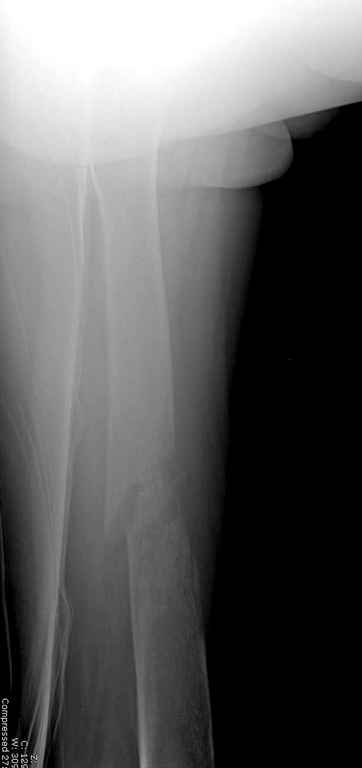

Здесь случай 66 летней пациентки со спонтанными болями в левой нижней

конечности, обратилась в приемное, сделаны снимки бедра и КТ.

Патологический перелом бедра, конечность на вытяжении.

Без определения характера и первоисточника опухоли стоит ли провести

остеосинтез? Рекомендации по вариантам остеосинтеза?

Имя     : Pathologic Femur injury lat.jpg